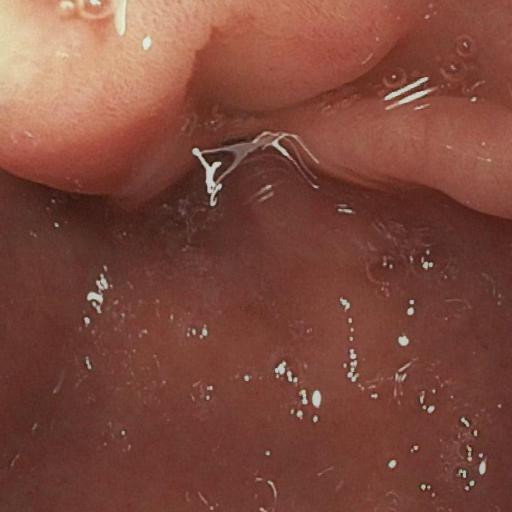

| (a) Input | (b) LIME | (c) HDRNet | (d) LECCM | (e) SwinIR | (f) NAFNet | (g) EndolMLE | (h) Ours | (i) GT |

The proposed method was evaluated on a synthetic dataset. All deep learning-based methods were fine-tuned based on E-kvasri. Figure 2 presents sample results of the proposed method and comparative methods on four endoscopic images from the E-kvasri.